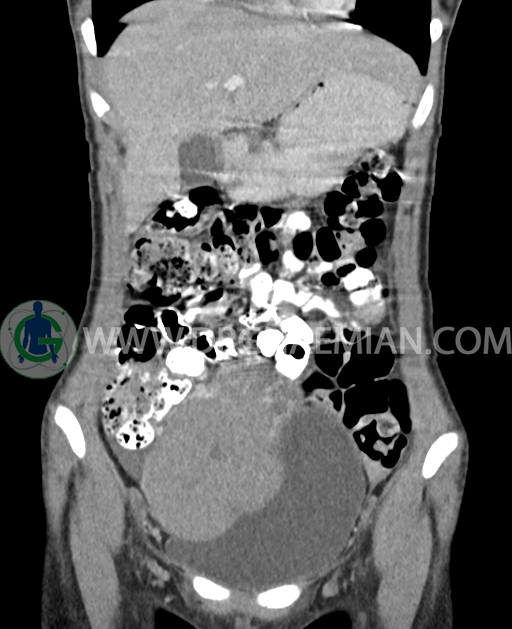

سی تی اسکن شکم و لگن از تشعشعات برای ایجاد تصاویر عرضی مقطعی از نایحه شکم و بین استخوان های لگن استفاده می کند. در این کیس تومور سلول زایا به ابعاد mm 125 x 112 x 80 دیده می شود.

در سی تی اسکن اسپیرال شکم و لگن با کنتراست خوراکی و وریدی (مولتی دیدکتور 16 با مقاطع ظریف و بازسازی های ساژیتال و کرونال) :

توده هیپردنس لوبوله بزرگ به ابعاد 125x112x80mm حاوی نواحی سیستیک داخلی و enhancement قابل توجه پریفرال همراه با آسیت متوسط در فضای شکم و لگن با احتمال بیشتر با منشا از تخمدان راست، درون لگن دیده می شود که در درجه اول مطرح کننده germ cell tumor می باشد .